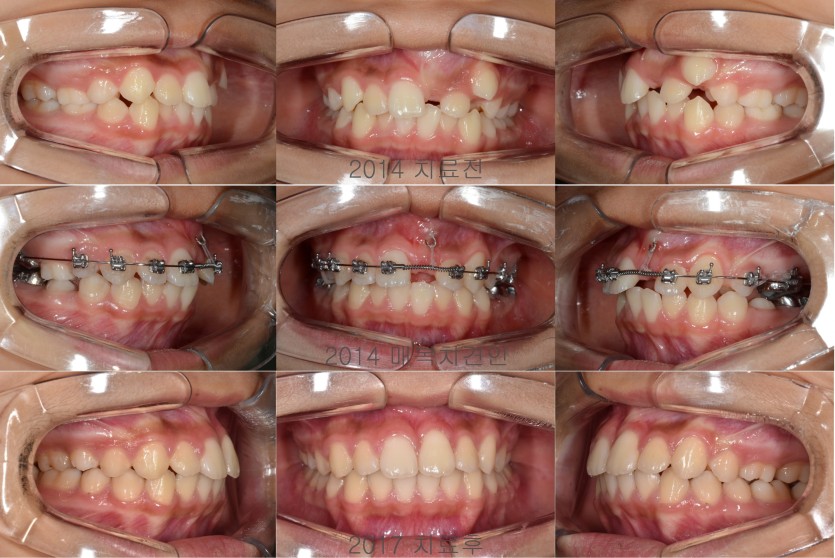

매복된 상악 중절치의 견인치료 150회

여러가지 이유로 매복된 치아들은 견인의 방법으로 해결해야 합니다.

매복된 치아들을 견인하기 위해서는 잇몸을 열어서 장치를 부착해야하는 소수술이 필요합니다.

장치를 부착하고 천천히 견인하되 견인방향과 배열을 위한 공간확보에 대한 고려가 필요합니다.